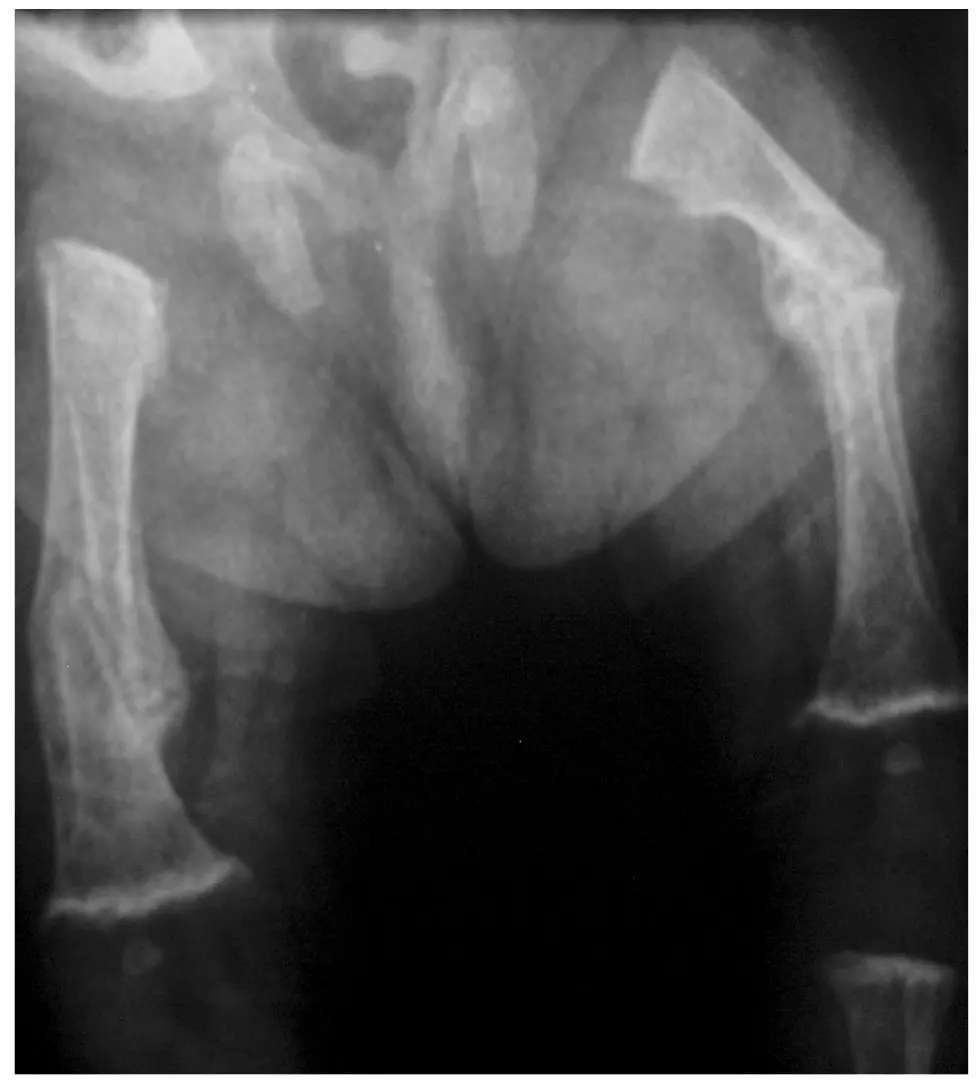

3,5-miesięczny wcześniak urodzony w 32. Hbd, z masą ciała 700 g, z obciążonym okresem noworodkowym (długotrwała mechaniczna wentylacja, BPD, długotrwałe żywienie pozajelitowe, cholestaza, nietolerancja karmienia) został przyjęty do naszej kliniki z powodu podejrzenia ciężkiej postaci krzywicy. Dziecko karmione Bebilon pepti MCT, otrzymywało 1500 IU/d witaminy D. Dwa tygodnie przed przyjęciem do kliniki doszło do obustronnego złamania trzonów kości udowych (w odstępie kilku dni) oraz złamania trzonu lewej kości ramiennej (ryc. 1, ryc. 2). W rejonie rozpoznano krzywicę z niedoboru witaminy D i włączono do leczenia witaminę D,

początkowo w dawce 10 000 IU/d (następnie 4000 IU/d), i przekazano dziecko do dalszej diagnostyki do IPCZD. Przy przyjęciu do naszej kliniki w badaniu przedmiotowym zwracały uwagę cechy wcześniactwa, cholestatyczne zabarwienie powłok skórnych, duża głowa z wydatnymi guzami czołowymi, duże ciemiączko (3 × 4 cm), majtki gipsowe na kończynach dolnych oraz opatrunek Desaulta na lewej kończynie górnej. Na podstawie wykonanych badań (tab. 7) postawiono u dziecka rozpoznanie osteopenii wcześniaczej związanej z niedoborem fosforanów. Oddalono podejrzenie krzywicy niedoborowej. W leczeniu zastosowano dietę bogatą w Ca i P (mleko dla wcześniaków) oraz prowadzono suplementację fosforanami drogą doustną. Z powodu hiperkalciurii odstawiono podaż witaminy D do czasu normalizacji wydalania Ca z moczem. Następnie włączono preparat 25-hydroksywitaminy i stosowano do czasu ustąpienia cholestazy. W trakcie suplementacji fosforanami obserwowano tendencję do niższych wartości Ca we krwi, co potwierdzało, iż u dziecka mamy nie tylko niedobory ustrojowe fosforanów, ale również wapnia. Do leczenia dołączono suplementację wapniem. Pozwoliło to na normalizację parametrów biochemicznych gospodarki Ca-P. Obserwowano również zrost kości długich, choć ze skróceniem kości udowych (przemieszczenie odłamów) (ryc. 3, 4).

Ryc. 3. Świeże złamanie trzonu kości udowej u dziecka z osteopenią wcześniaczą

Ryc. 4. Złamanie trzonów kości udowych – widoczny zrost ze skróceniem kończyn (L > P)